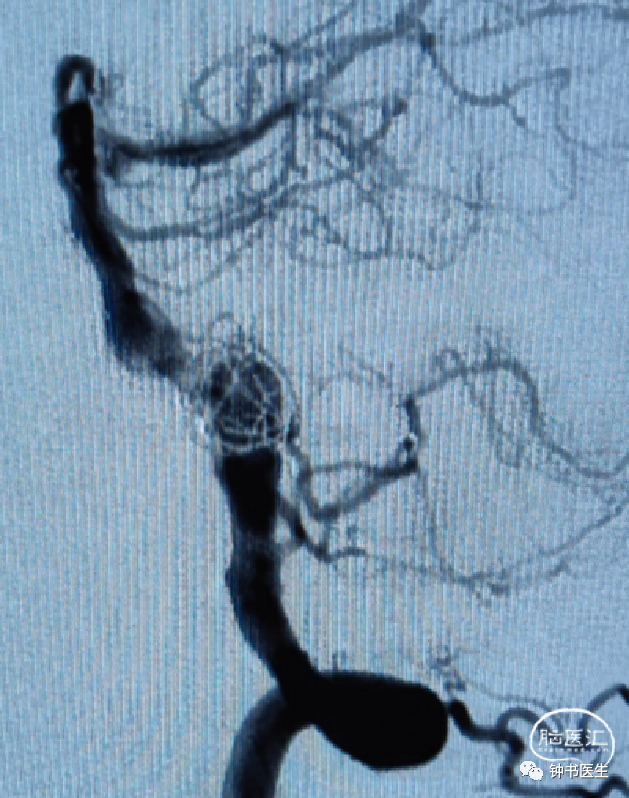

椎基底夹层动脉瘤:65Y M,脑干梗塞

术后患者无明显不适(TB 6.0X45)

焦点1:血流导向装置是否可以在后循环使用?